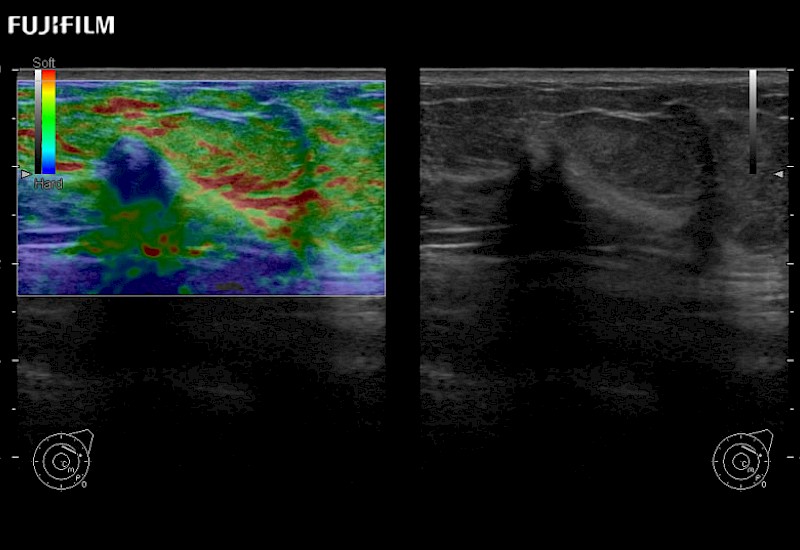

The ARIETTA 750 incorporates all of the proven technologies and functions that medical professionals have come to expect from Fujifilm Healthcare.

ARIETTA 750 is the definitive diagnostic ultrasound solution for any clinical setting - Private Office, Imaging Center, or Hospital. The ARIETTA platform provides the ultimate in clinical performance with its state-of-the-art features and large user-friendly display.

The ARIETTA 650 DI combines trusted Fujifilm Healthcare technologies and features tailored for surgical oncology.

Designed to meet the demands of surgeons, the ARIETTA 650 DI offers precise guidance. Its advanced capabilities and large, intuitive display offer accurate and efficient care in operating rooms and specialized surgical settings.

Learn moreFujifilm Healthcare continues to listen to the experts, our neurosurgeons, by developing an ultrasound system specifically designed for the Operating Room.

Guidance is the fundamental purpose for all of our surgical ultrasound technology. Fujifilm Healthcare is committed to designing tools that help neurosurgeons navigate inside the human body and provide the necessary information to immediately make critical surgical decisions.

With the ARIETTA Precision the next level of surgical ultrasound is here.